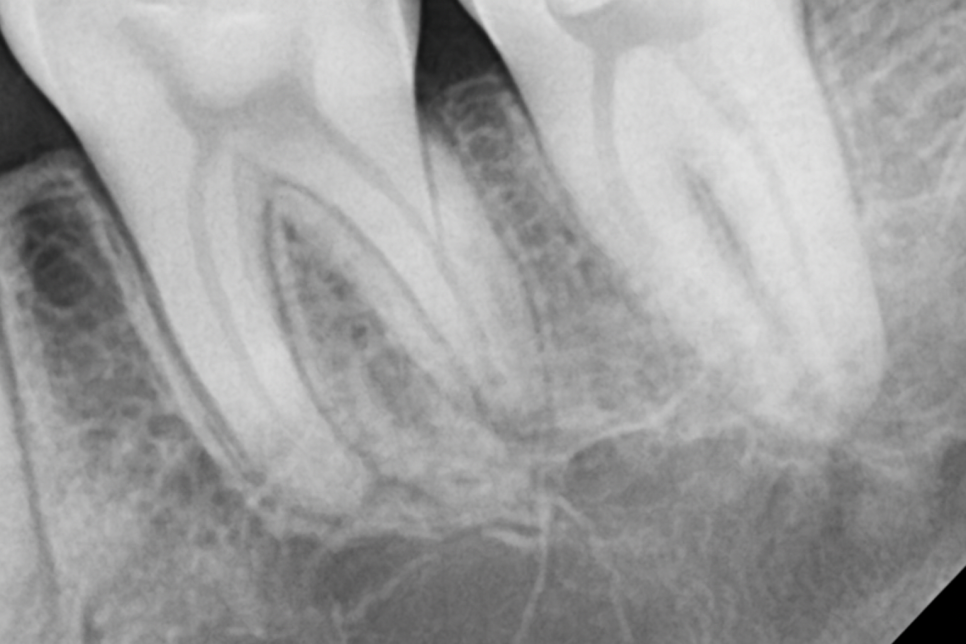

근관은 매우 다양하게 생겼습니다.

당산동 치과 에서 준비한 사진을 보시면 그 다양성이 한눈에 이해되시죠?

대개 뿌리가 곧게 뻗어져 나가는 반면,

C자 모양으로 만곡되어 있는 케이스는

치수가 서로 얽혀 있어 감염된 부위를 깨끗하게

소독하는 단계가 어렵습니다.

당산동 치과 에서 준비한 사진처럼

서로 연결되어 있거나 넓게 펼쳐져 있는 형태를 갖고 있기에

입구를 찾는 것부터 어렵습니다.

당산동 치과 에서 준비한 사진에서 보이는

두 개의 치아 가운데 하나는 C형 근관입니다.

이 사진 하나만으로는 이를 판단하긴 어렵습니다.